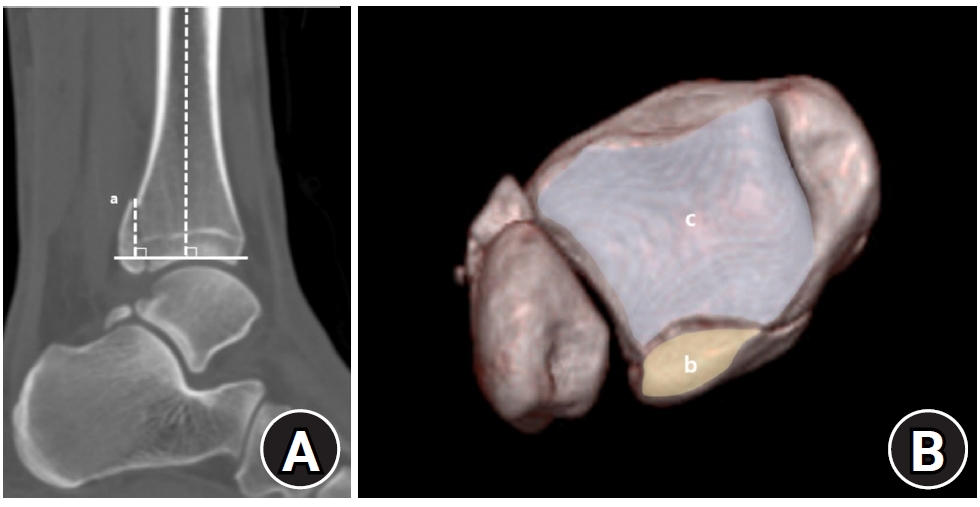

Posterior malleolar fracture morphology was classified according to the Haraguchi and Bartonicek systems (Figs. 2, 3) [19,20]. The peak height of the posterior malleolar fracture was measured as the vertical distance from the highest point of the distal tibial articular surface to the fracture apex in the sagittal plane (Fig. 4A). The articular surface area of the posterior malleolar fragment was calculated using the region of interest tool in a picture archiving and communication system (Maroview 5.4; INFINITT Healthcare) (Fig. 4B). All quantitative radiographic measurements were performed by two orthopedic surgeons; mean values were used. For categorical variables, disagreements were resolved by consensus.

Fig. 4.

(A) Peak height (a) of the posterior malleolar fracture is defined as the vertical distance from the highest point of the distal tibial articular plafond to the apex of the posterior malleolar fragment on the sagittal plane. (B) The articular surface area (mm2) of the posterior malleolar fracture fragment (b) was measured using the region of interest tool in a picture archiving and communication system. Articular involvement (%) was calculated as the ratio of the fractured area (b) to the total tibial plafond articular surface area (b+c).

jmt-2025-00234f4.jpg